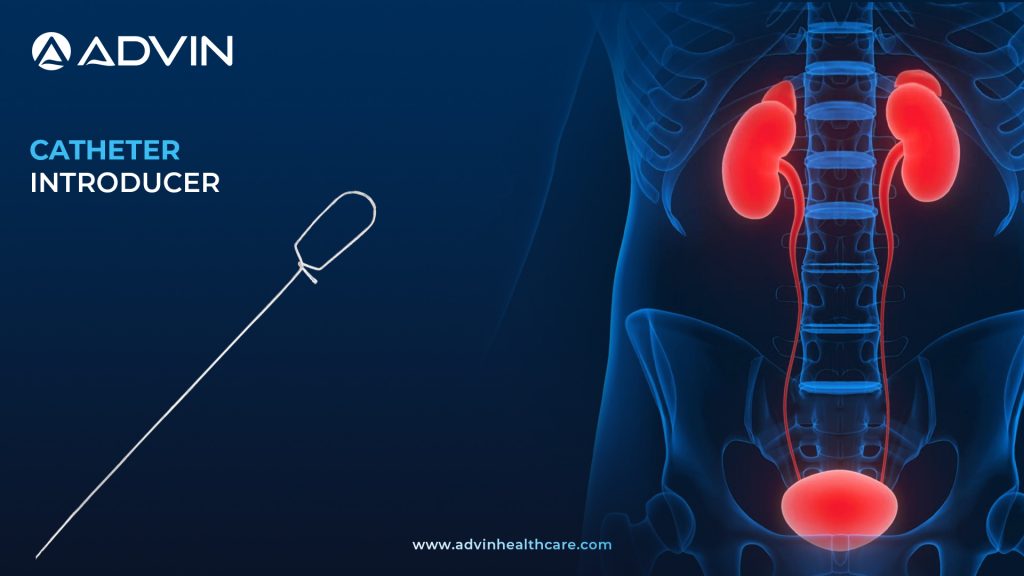

Catheter Introducer – Safe and Controlled Vascular Access Made Easy

Introduction to Catheter Introducer: Seamless Access for Safe Catheter Placement A Catheter Introducer is a medical device used to guide urinary catheters into the urethra or bladder smoothly and safely. It minimizes resistance during insertion and helps prevent trauma to the urethral lining. This device is commonly used in cases...